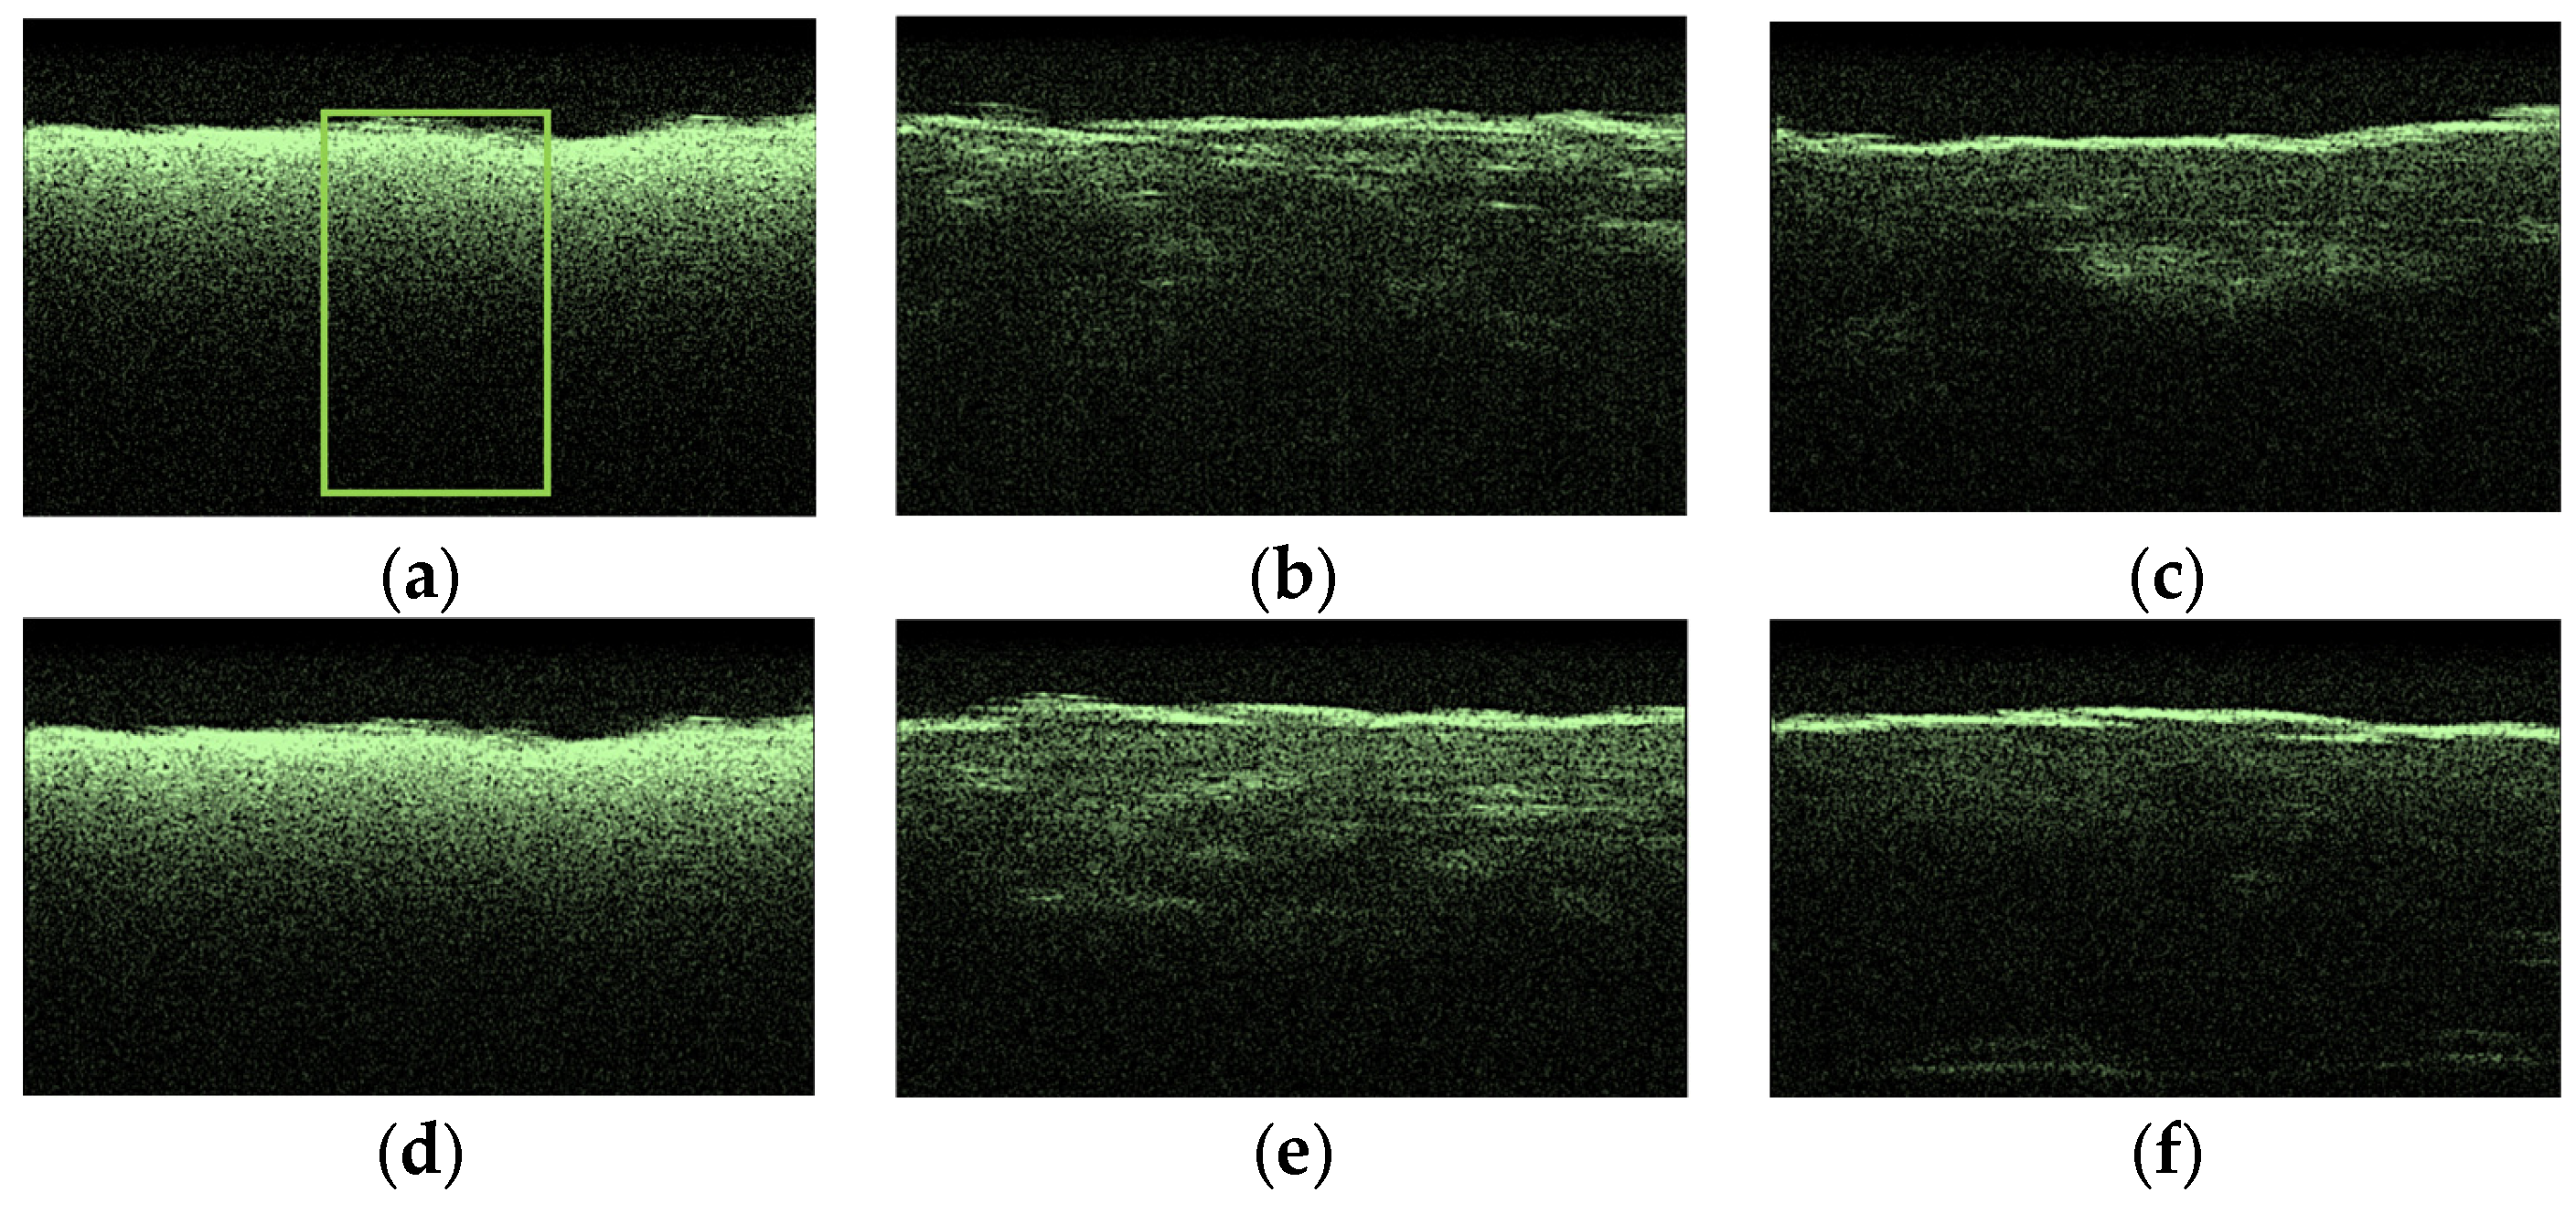

To compare the obtained OCT images, OCA samples were selected, which showed the lowest and highest diffusion coefficients of the studied collagen materials. Figure 9 shows typical OCT images for the “PER uncrosslinked” samples for this series of experiments. The rectangle marks the area of averaging of the OCT signal (51 A-scan), which was selected in the region of interest.

Figure 9.

Typical OCT images of “PER uncrosslinked” samples: dry (a), after exposure to saline (b), after subsequent exposure to 20% aqueous glucose solution (c); dry (d), after exposure to saline (e), after subsequent exposure to 32% aqueous glucose solution (f).

After analyzing the OCT images and averaged A-scans shown for “PER uncrosslinked” samples in Figure 9 and Figure 10, we were convinced that a 32% aqueous glucose solution was more effective than a 20% solution.